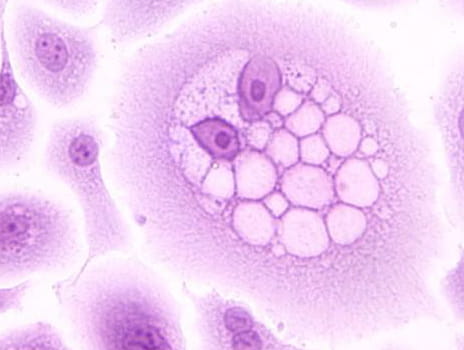

Nearly 80 million Americans – 1 out of every 4 people – are infected with HPV, a virus that causes several types of cancers. Of those millions, more than 36,000 will be diagnosed with an HPV-related cancer this year. Despite those staggering figures and the availability of a vaccine to prevent HPV infections, HPV vaccination rates remain significantly lower than other recommended adolescent vaccines in the U.S. Even before the COVID-19 pandemic, HPV vaccination rates lagged far behind other vaccines and other countries’ HPV vaccination rates. According to 2019 data from the Centers for Disease Control (CDC), slightly more than half (54%) of adolescents were up to date on the HPV vaccine.